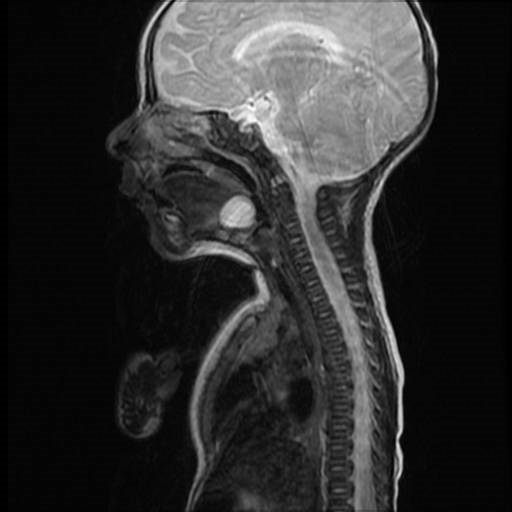

A 45-day-old baby presented with respiratory distress, chest in-drawing, and stridor since birth. She was a full-term female baby with no dysmorphic features (Fig. 1A). The lesion was misdiagnosed elsewhere as laryngomalacia and spontaneous recovery were assured without intervention. Endoscopic evaluation was not done. The baby was brought to our center due to failure to thrive, feeding difficulty, repeated choking episodes, and worsening physical findings. Preoperative fiber optic laryngoscopy was done which revealed a cystic lesion at the vallecula obstructing the laryngeal inlet, pushing the epiglottis forward (Fig. 2). MRI scan showed a well-defined non-enhancing thin-walled cystic lesion measuring 14.8x14.2mm at vallecula and the diagnosis was confirmed (Fig. 3). Surgery was planned. Intubation was attempted but failed. The baby was tracheostomized before the procedure for ventilation, anticipating postoperative surgical site edema as well. Uncuffed tracheostomy tube size 3 was used. A direct laryngoscope straight blade with zero degree endoscope was held by the anesthetist to view the cyst and the EVAC-70 coblation wand was held in the right hand by the surgeon. The settings of the coblator were maintained at 70-30, coblation and coagulation respectively. The wand was used in both coblator and coagulation mode based on need. The anterior cyst wall was completely removed by coblation, and the cyst was thus marsupialised. Bleeding points were coagulated using the same wand. The child was attached to the ventilator immediately and was taken off on a postoperative day 1. The tracheostomy tube was closed on day 2 and removed on postoperative day 3. Postoperative recovery was uneventful and the general condition improved considerably. Stridor completely disappeared on day 5 (Fig. 1B).

Figure3

MRI Showing Cyst.